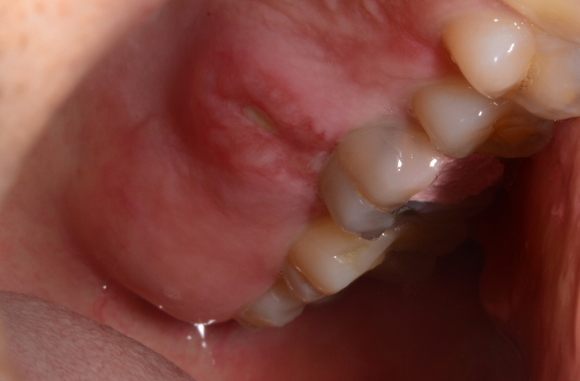

두 번째로 열성 수포라고 불리는 구순 포진은 입술이나 그 부근으로 생기는 수포성 궤양이예요. 구순포진은 헤르페스 바이러스 감염에 의해 생기는 질환입니다. 타인과의 접촉으로 인해 감염되는데있다는데, 경로는 피부 점막을 동원해서라고 해요. 헤르페스 바이러스는 한번 감염되면 평생몸육체에 잠복하고 있다가 그런 순간마다 재발할 수 있습니다.

스트레스, 피로, 발열, 많은 햇빛 노출, 영양 부족, 수면 부족, 감기, 독감 등 면역력이 약해질 때, 생리 등 호르몬 전환가 있을 때에 재발합니다.